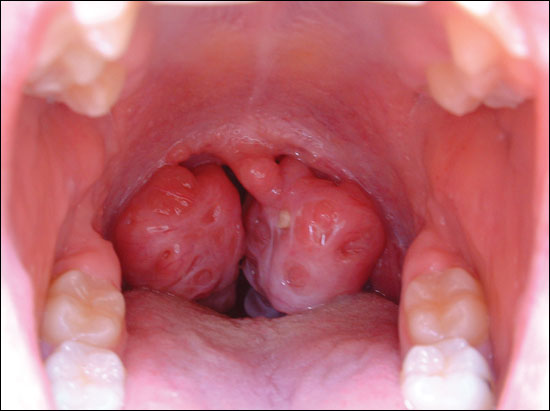

ثانياً : في حالة تضحم اللوزتين بشكل مزعج للمريض مما يسبب له انسداد في مجرى الهواء أو صعوبة في بلع الطعام ... أو شخير بالإضافة الى تقطع النوم ( ما يسمى باختناق النوم ) ففي هذه الحالة يتم ازالة اللوزتين .. من باب ازالة السبب.

تضخم حاد بالوزتين .. يصيب الأطفال أكثر من البالغين